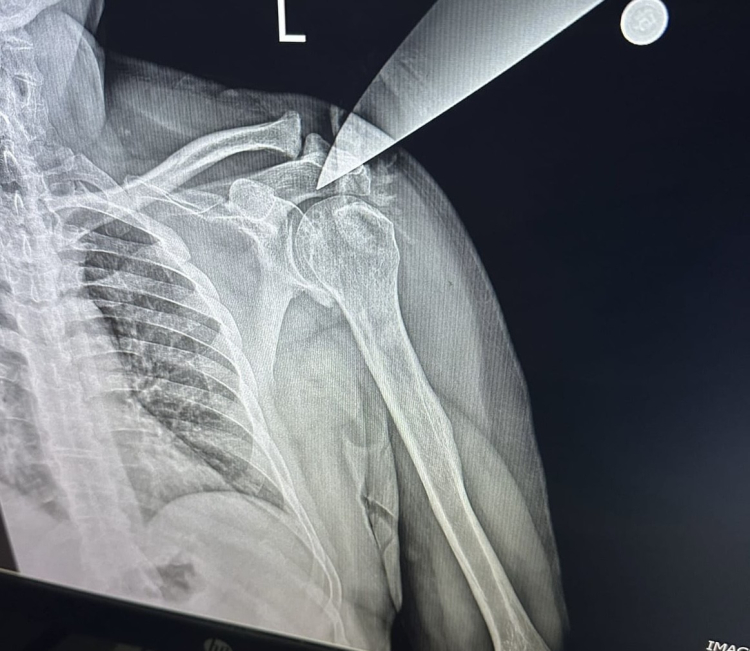

Edinilen bilgiye göre, Bursa'nın Yıldırm ilçesinde özel bir diş kliniğine 3 çocuğuyla birlikte gelen H.H.Y. (25) adlı kadın, bir süre diş doktoru Hakkı Nail Ö. ile konuştu. Yoğunluk olduğu için alamadığını ifade eden doktoru arkasını döndüğü esnada çantasında taşıdığı bıçakla saldıran kadın, bıçağı Hakkı Nail Ö.'nün omzuna saplayıp çocuklarını da bırakıp kaçtı. Korku dolu anlar yaşayan doktor ve klinikteki meslektaşları, 112 ekiplerini aradı. İhbar üzerine olay yerine gelen sağlık ekipleri, yaralı doktoru Yüksek İhtisas Eğitim ve Araştırma Hastanesine sevk ederken, doktorun omzuna saplanan bıçak ameliyatla alındı.